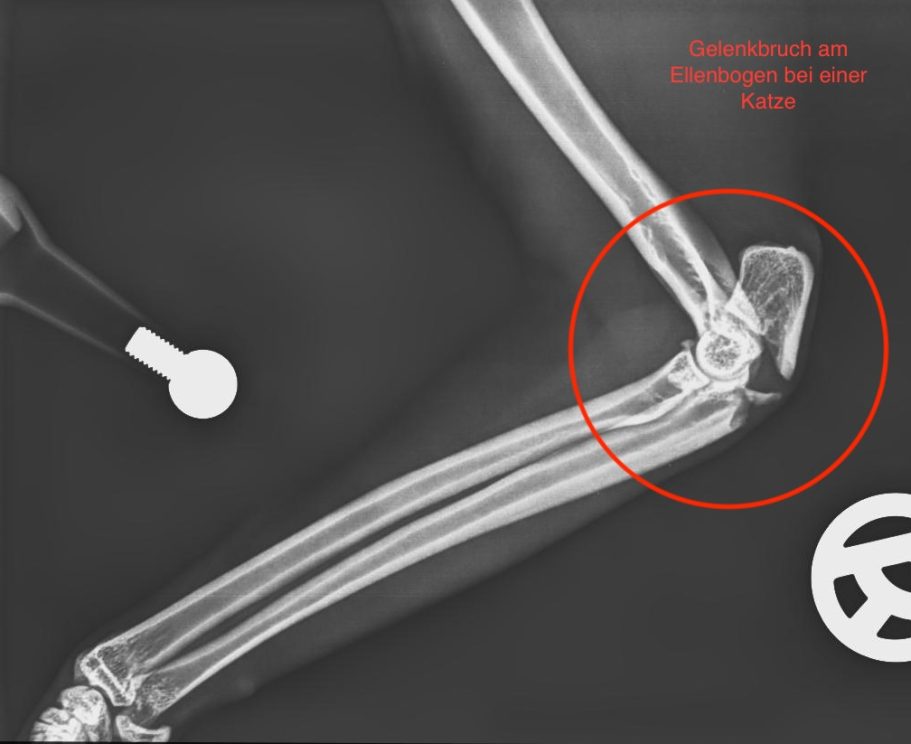

Frakturversorgung (Knochenbrüche)

Behandlung von Frakturen bei Hunden und Katzen mittels moderner Verfahren.

Ziel ist eine stabile Fixation, eine schnelle Heilung und die möglichst frühzeitige Wiederherstellung der Belastbarkeit.

Frakturversorgung mit Arthrex Implantate

Für die Behandlung von Knochenbrüchen verwenden wir moderne Implantate von höchster Qualität. Sie bieten eine sehr gute Stabilität und unterstützen eine sichere Heilung. Je nach Art der Fraktur kommen Implantate aus Titan oder hochwertigem chirurgischem Edelstahl zum Einsatz. Die Implantate sind in passenden Größen verfügbar und genau auf den Knochen und die Anatomie Ihres Tieres abgestimmt.